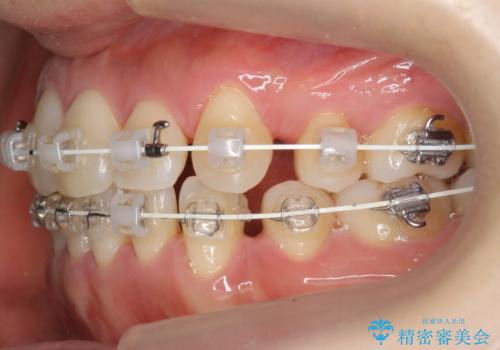

- 矯正装置

- ワイヤー矯正

- 八重歯と上下の正中のずれを気にして来院。

上の前歯の正中が右にずれていました。

小臼歯抜歯を行い、ワイヤー矯正を行いました。